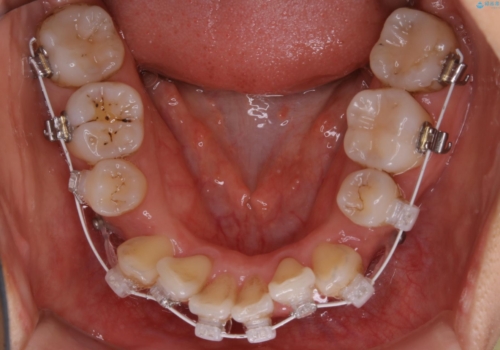

- ワイヤー(審美装置)

- 以前からコンプレックスだった八重歯の治療を主訴にご来院されました。

検査の結果、抜歯をすることでスペースを作って並べる方法が選択され、ワイヤー装置を用いた治療を開始することとなりました。

奥歯の上下のズレ等は軽度で、必要なスペースと抜歯により作られるスペースがほぼ等量だったため治療の単純化が計れ、大きな移動・見た目の劇的な変化に対して比較的早期での治療完了となりました。

叢生の度合いが重く、抜歯が必要なケース。八重歯の部分以外には大きな問題は認められなかったため、劇的変化が起こる治療でも比較的短期間で終了することができました。